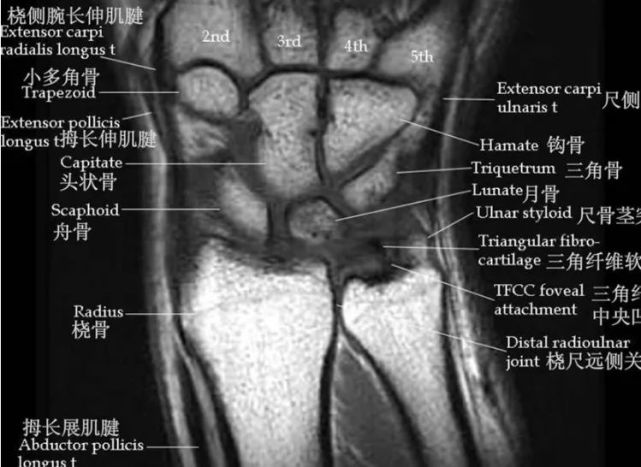

腕关节核磁共振图讲解

腕关节磁共振mri解剖冠状

【高清mri图】腕关节磁共振mri解剖